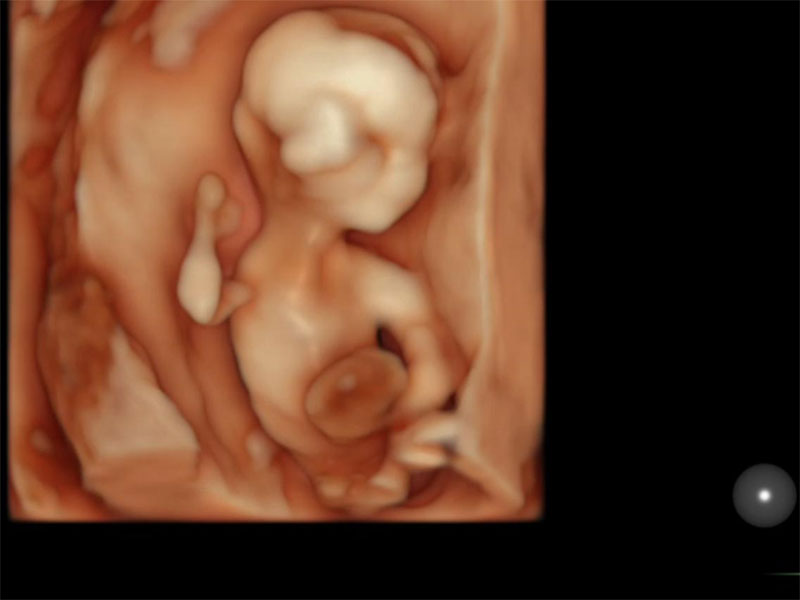

Görsel notu: 12.haftada çekilmiş 3D ultrason görüntüsü (transvajinal US ile)

- En iyi sonuçlar, transabdominal (karın üzerinden) ve/veya transvajinal (vajinal yoldan) muayenenin birlikte kullanımı ile sağlanır. Farklı fetal yapıların görüntülenmesi, rahmin konumu, fetüsün konumu ve annenin karın duvarı kalınlığı ve kilosu gibi birçok faktöre bağlıdır.

- Transvajinal ultrason muayene isteğe bağlıdır; genellikle yüksek çözünürlüklü problarla yapılan transabdominal tarama bebeğin kapsamlı bir kontrolü için yeterlidir.